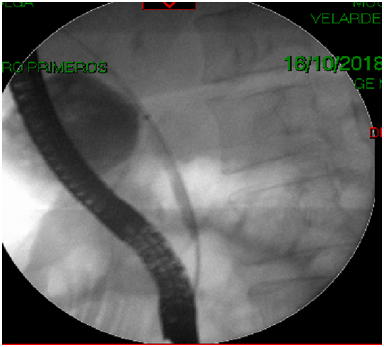

68-year-old female with presence of secondary hypothyroidism 8 years of evolution in treatment with levotiroxin, systemic hypertension 2 year of evolution treated with losartan, thyroidectomy 8 years ago, c-sections 243 and 38 years ago, the patient denies the use of alcohol or tobacco. Initiates with sudden transitive pain in epigastrium, vomiting several times, undergoing imaging and laboratory tests diagnosing pancreatitis its determined that the patient is in need of a ERCP, which is performed at a private institution, during the procedure the major duodenal papilla is identified anatomically normal but without bile output with multiple cannulation attempts (Figure 1), continuing with procedure applying contrast appreciating two gallstone suggesting images in distal choledocus which measures 9 mm in diameter (Figure 2) with a probable stenotic area in the distal portion, a wide sphincterotomy is performed with posterior passing of extraction balloon doing multiple sweeps obtaining two 7 mm gallstones due to said area of stenosisa 10 fix 10 cm stent is placed towards the right hepatic duct. After the procedure the patient presents moderate to intense pain in right hypochondrium alongside hypotension, administrating crystalloids and vital sing stabilization ordering CT scan where a sub capsular collection is visualized, varying heterogenicity from 600 to 20 HU, highly suggestive of a serohematic component with approximate size of 17 by 13.8 by 6.5 cm, with approximate volume of 820 cc (Figure 3) (Figure 4) with diagnosis of a probable subcapsular hematoma, with later presentation of acute kidney failure requiring temporary renal substitution therapy, once she was hemodynamically stable its moved to our unit to continue treatment, taking laboratory exams determining hyperbilirubinemia, due to conjugated bilirubin and elevated liver enzymes, deciding to do new CT scan where a 20% diminution of hematoma size is appreciated and adding pleural effusion to the findings deciding to give a conservative management, eight days later performing control ultrasound finding hematoma with a tendency to re absorption .

Figure 1 Endoscopic retrograde cholangiopancreatography: Canned oddi sphincter.

Figure 2 Fluoroscopy with introduction of the guide.